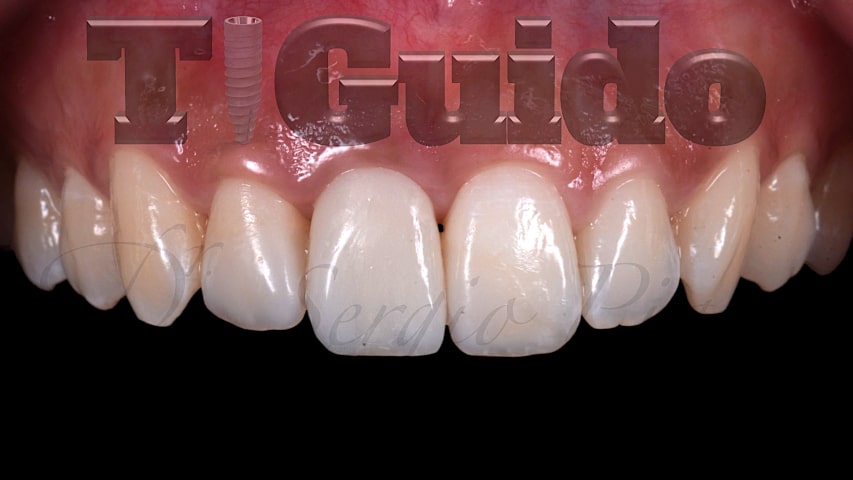

Alcuni nostri casi